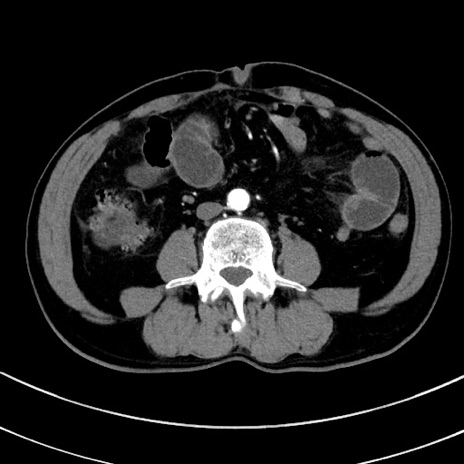

症例8(横断像)

【症例】 60歳代男性

【主訴】 黒色吐物

【現病歴】 4日前から嘔気自覚、2日前の朝食後にも嘔気あり、自分で手で嘔吐反射起こし嘔吐したところ血が混ざっていたため受診。

【既往歴】 5年前汎発性腹膜炎を伴う急性虫垂炎で手術、高血圧、前立腺肥大症、高脂血症

【身体所見】 腹部正中に手術癩痕あり 腹部平坦・軟圧痛なし膨満感あり

【データ】WBC 8400、CRP 4.54